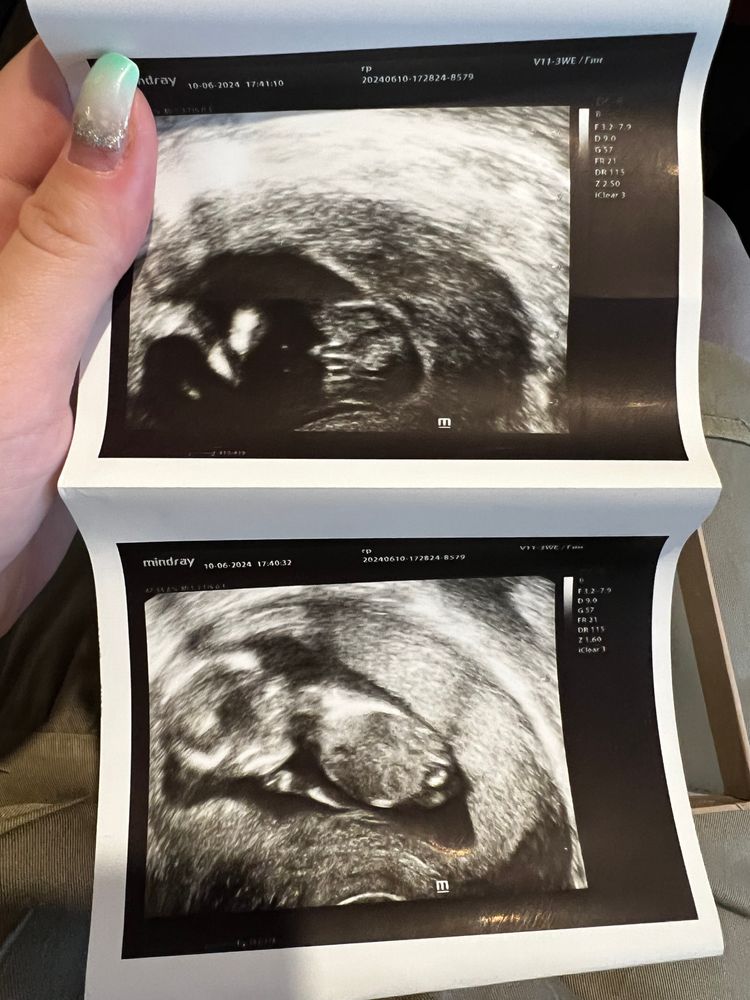

Всем привет! Хотела поделиться радостной новостью - точнее двумя🤍 Вчера была на узи, плацента (хорион) поднимается и пол определили - сыночек 🩵 фото приложу) Пол сказали в 13.6 недель) вот теперь думаю, не ошиблись?) Хотя узист очень опытная и сначала сомневалась, но потом он повернулся и стало хорошо видно, она без сомнений сказала пацан 🤭

На первом фото справа) я так поняла, он сначала ножки поджимал, фото сделали как бы сбоку что ли 😊

Кошка В Сапожках, я прям отчетливо вижу(как показала узист) достоинство, хотя мама и муж не видят, думают что не точно еще)) особенно на первом фото прям в разрезе